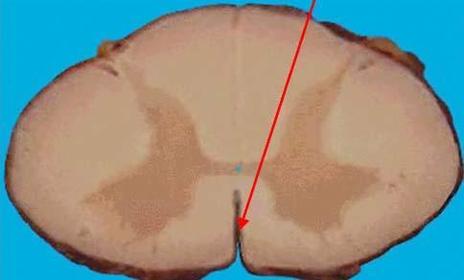

Anterior Horn (ventral) Innervates skeletal muscles

Lateral HOrn Innervate cardiac muscles.

Posterior Horn (Dorsal) Receives sensory info. like touch.

Gray Commissure communication route between R&L sides of gray matter.

White commissure Connects the white matter to the R&L sides of spinal cord.

Anterior Funiculus Lateral Funiculus posterior Funiculus Transmit nerve impulses vertically along spinal cord.

Anterior median fissure Divides spinal cord into 2 anterior sections

Posterior median sulcus median portion of the spinal nerves enter the spinal cord.

central canal houses the spinal cord and CSF fluid